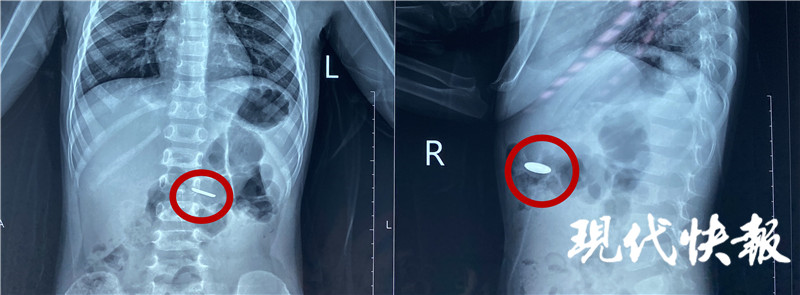

4月20日,江蘇淮安,小豪的家人在收納玩具的時候,發(fā)現(xiàn)常用的遙控器里的一顆紐扣電池不見了,家人的第一反應(yīng)是電池被小豪吃了,趕緊帶著他前往醫(yī)院。經(jīng)過緊張的手術(shù),醫(yī)生從2歲男童小豪(化名)的小腸內(nèi)取出一枚紐扣電池,電池周圍的腸壁被腐蝕發(fā)黑。

“當(dāng)時拍了片子發(fā)現(xiàn)電池在胃部,消化內(nèi)科的醫(yī)生及時給他做了胃鏡檢查,這個電池比較小,已經(jīng)快速排空進(jìn)入了小腸,胃鏡沒有發(fā)現(xiàn)電池。后來又拍片檢查,確認(rèn)電池已經(jīng)進(jìn)入小腸,就轉(zhuǎn)入外科進(jìn)行手術(shù)治療。”淮安市婦幼保健院小兒外科主治醫(yī)師顧春暉說。

完善手術(shù)準(zhǔn)備,醫(yī)生通過腹腔鏡將電池取出。“這個手術(shù)本身比較困難,因?yàn)檫@個電池非常薄,直徑只有1厘米左右,小腸非常長,我們用了很長時間才找到這個電池,電池附近的腸道黏膜已經(jīng)發(fā)黑,形成了化學(xué)性的腐蝕,如果時間再長一點(diǎn)可能造成穿孔等一些非常嚴(yán)重的后果。”顧春暉說。